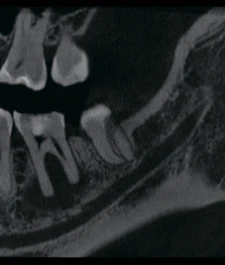

Изображения с высоким разрешением для точной диагностики

Получите исключительную чёткость изображения и настраиваемый объём сканирования с помощью RAYSCAN. Адаптируйте свои снимки в соответствии с вашими конкретными клиническими потребностями, и будьте уверены в том, что запечатлеете каждую сложную деталь и раскроете безграничные возможности.

FOV 10×10 см, 160 μm

FOV 4×5 см, 70 μm